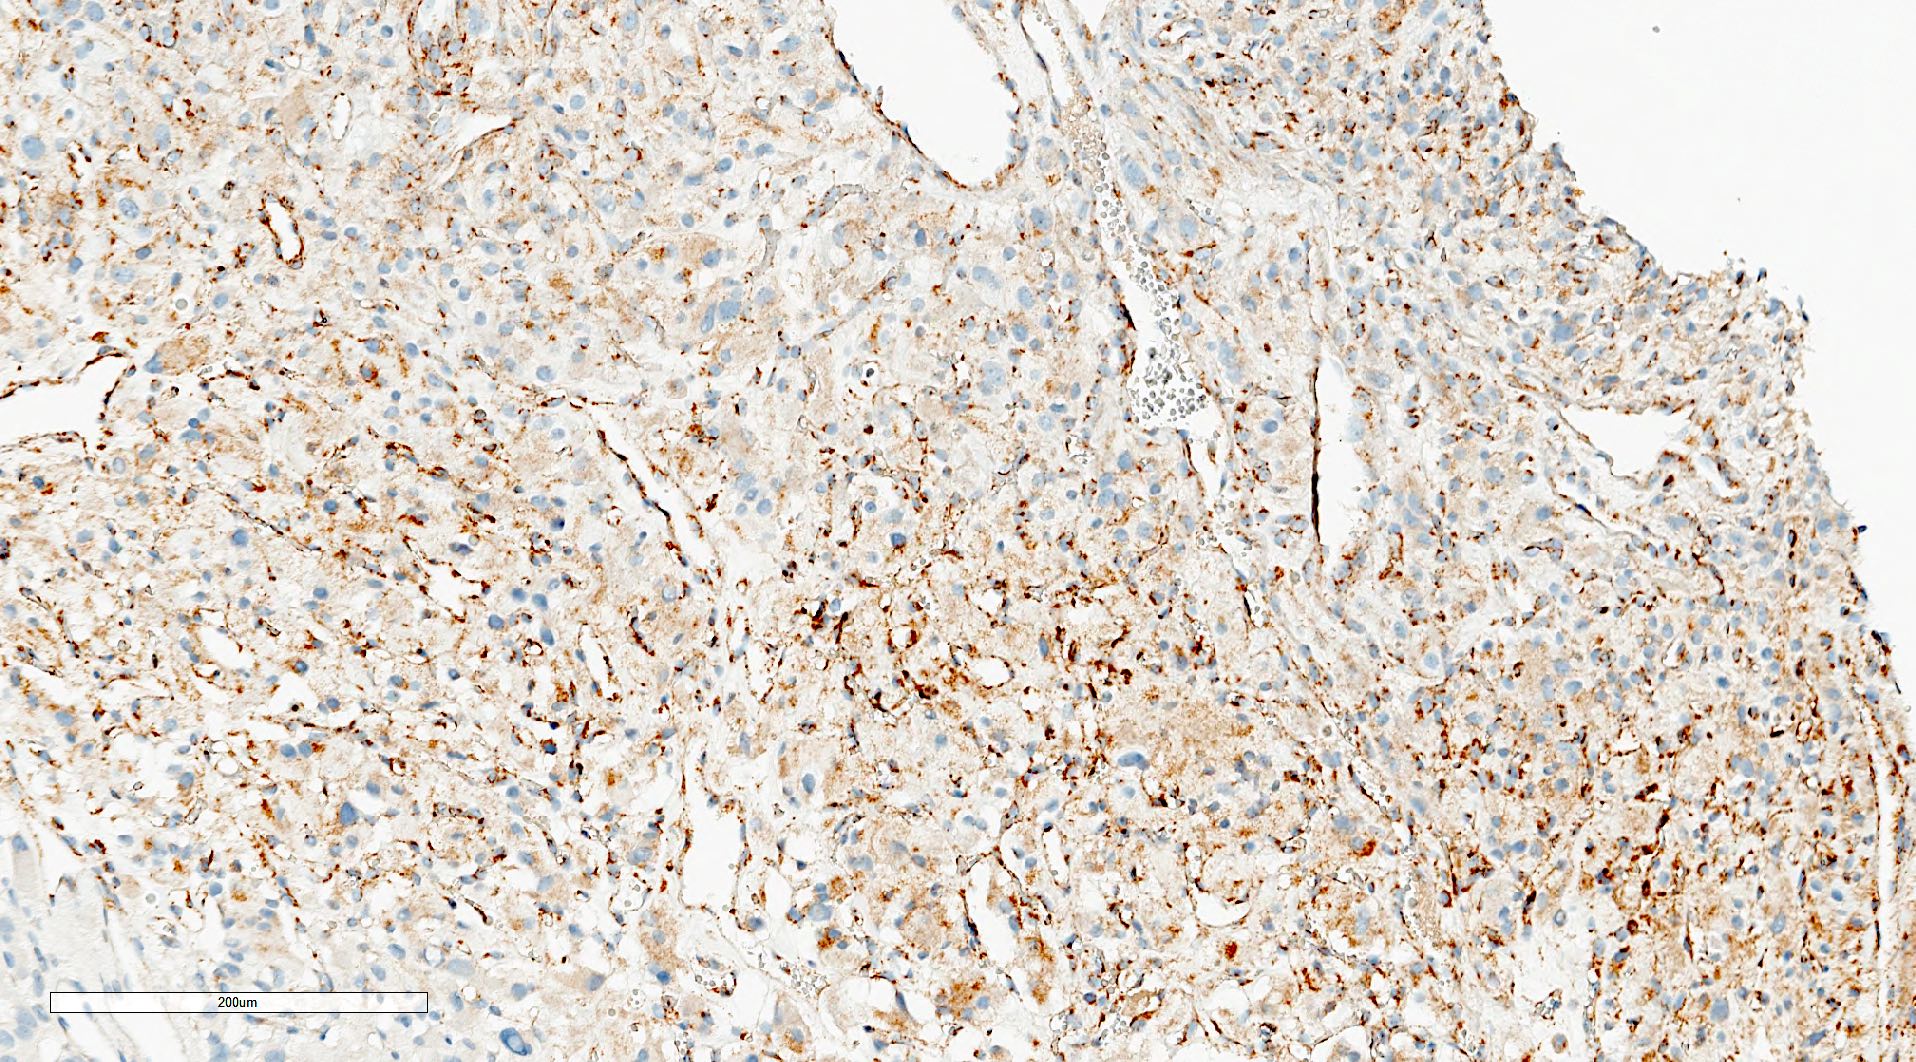

- Classic histologic morphology: monomorphic cells with abundant eosinophilic / amphophilic cytoplasm arranged in a nested / zellballen pattern and separated by fibrovascular septa with sustentacular cells

- Typical morphology: epithelioid cells with abundant, eosinophilic / amphophilic, granular cytoplasm and round / ovoid, vesicular / salt and pepper nuclei, arranged in a nested / zellballen pattern and separated by fibrovascular septae with sustentacular cells (Am J Surg Pathol 2004;28:94, World J Clin Cases 2014;2:591, Endocr Pathol 2022;33:90)

- May have focal pleomorphism, nuclear hyperchromasia, low mitotic activity or clear cytoplasm

Microscopic (histologic) images

Contributed by Theodorus H. van der Kwast, M.D., Ph.D., Michelle R. Downes, M.D., Debra L. Zynger, M.D. and David Cohen, M.B.B.Ch., M.D.

- Sustentacular cells: S100, SOX10

- Microscopic description: This specimen shows an unencapsulated, monomorphous population of round tumor cells in a nested / zellballen pattern with delicate vascular septa and intervening extravasated red blood cells. It predominantly involves the lamina propria of the bladder but in 1 tissue piece clearly involves muscularis propria. The tumor cells have abundant amphophilic cytoplasm and vesicular chromatin with occasional small nucleoli. There is no necrosis, diffuse growth pattern or vascular space invasion identified. The mitotic count is (maximally) 1/10 high power fields. Immunohistochemistry shows the tumor cells to be positive for GATA3 with strong and diffuse expression of synaptophysin and chromogranin, as well as retention of SDHB staining. The tumor cells are negative for AE1 / AE3, HMWK and p63. The Ki67 proliferation index is < 1%. S100 shows faint nuclear and cytoplasmic staining with occasional sustentacular cells identified.

- Microscopic description: Sections show unremarkable surface urothelium with a lesion in the deep lamina propria comprised of large eosinophilic cells with hyperchromatic, focally enlarged nuclei with occasional intranuclear inclusions. A fine vascular plexus is identified in some areas. Necrosis and hemorrhage are not identified. Mitotic rate = 1/10 high power fields (field of view [FOV] = 0.55 mm). The lesion extends to the cauterized base of the specimen. Immunostains confirm the lesion expresses synaptophysin, chromogranin and GATA3. SDHB is retained. AE1 / AE3, CD45, p63 and NKX3.1 are negative.